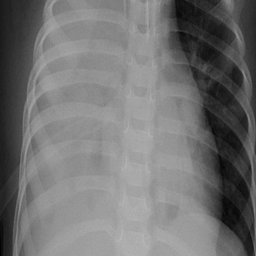

Refer to caption

Figure 4: Segmentation masks of OCT data, where fθf_{\theta}^{\star}italic_f start_POSTSUBSCRIPT italic_θ end_POSTSUBSCRIPT start_POSTSUPERSCRIPT ⋆ end_POSTSUPERSCRIPT outperforms fθf_{\theta}italic_f start_POSTSUBSCRIPT italic_θ end_POSTSUBSCRIPT.

Figure 5: Segmentation masks of Dermoscopy data, where fθf_{\theta}italic_f start_POSTSUBSCRIPT italic_θ end_POSTSUBSCRIPT outperforms fθf_{\theta}^{\star}italic_f start_POSTSUBSCRIPT italic_θ end_POSTSUBSCRIPT start_POSTSUPERSCRIPT ⋆ end_POSTSUPERSCRIPT.

The results show that edge-enhanced pre-training yields significant performance improvements in certain imaging modalities while degrading segmentation quality in others. Exemplary cases, where both fθf_{\theta}^{\star}italic_f start_POSTSUBSCRIPT italic_θ end_POSTSUBSCRIPT start_POSTSUPERSCRIPT ⋆ end_POSTSUPERSCRIPT and fθf_{\theta}italic_f start_POSTSUBSCRIPT italic_θ end_POSTSUBSCRIPT significantly outperform each other can be seen in fig.˜4 and fig.˜5. This variability highlights the importance of aligning preprocessing strategies with the inherent characteristics of each modality rather than applying a uniform approach. Through the analysis of statistical meta-features—standard deviation and image entropy—, we identified indicators for anticipating when edge emphasis would be advantageous. Leveraging these indicators, we developed a selection mechanism that outperforms generic pre-training strategies, optimizing segmentation accuracy. While we focussed on the meta-features standard deviation and entropy due to the closeness to pixel intensities, which are determined by the use of edge operators, we encourage further work on higher-dimensional methods for meta-classification like a shallow convolutional neural network or an image encoder. Given that no universally optimal edge filter exists for all images [13], achieving consistent cross-modality improvements in segmentation quality presents a considerable challenge. With the specific edge kernel used in data pre-processing for foundation models vastly determining performance gains and losses, different edge kernels like Sobel [6] or Prewitt [16] should be examined to identify influences in performance. Since applying edge enhancement in pre-training of foundation models exhibiting great performance increase, we suggest further research on the application of edge enhancement in the subsequent fine-tuning of foundation models. Integrating multiple filters within a unified model selection framework could also improve adaptability. Alignment between certain edge filters and certain imaging modalities pose vast potential for futher increase in segmentation performance. Moreover, applying edge enhancement not only at the pre-training stage but also during subsequent refinements remains an avenue for future work. While we validated the benefits and restrictions of using edge-enhanced data in pre-training of foundation models, we recommend further work on increasing computation efficiency due to increased training needs for two foundation models. In this paper, we propose applying edge enhancement on image data in pre-training of foundation models for improved cross-modality segmentation quality. By leveraging meta-features such as standard deviation and image entropy, we develop a meta-classification strategy to selectively apply edge-enhanced pre-training, achieving an cross-modality segmentation performance improvement by 16.42% compared to models pre-trained on edge-enhanced data only and 19.30% compared to models pre-trained on raw data only. For the modalities Fundus, Mammography, US, and XRay, vast performance gains can be achieved using our meta-classification strategy, while for OCT we recommend solely using edge-enhanced data in pre-training. Our work provides a principled framework for optimizing segmentation performance by aligning pre-training strategies with the intrinsic properties of medical imaging modalities, offering a significant step forward in the development of robust, generalizable foundation models for medical image analysis.